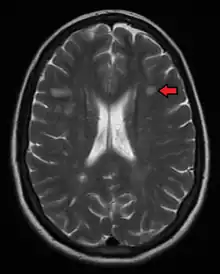

MRI

Magnetic resonance imaging (MRI) of the brain and spine may show areas of demyelination (lesions or plaques). Gadolinium can be administered intravenously as a contrast agent to highlight active plaques, and by elimination, demonstrate the existence of historical lesions not associated with symptoms at the moment of the evaluation.[103][104]